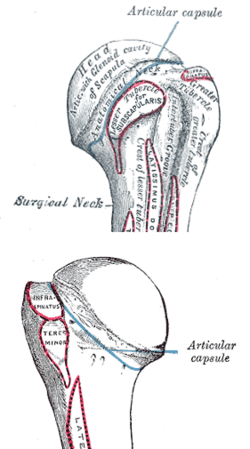

Humeral head

The head (caput humeri), is nearly hemispherical in form. It is directed upward, medialward, and a little backward, and articulates with the glenoid cavity of the scapula to form the glenohumeral joint (shoulder joint). The circumference of its articular surface is slightly constricted and is termed the anatomical neck, in contradistinction to a constriction below the tubercles called the surgical neck which is frequently the seat of fracture. Fracture of the anatomical neck rarely occurs.[1] The diameter of the humeral head is generally larger in men than in women.

Anatomical neck

The anatomical neck (collum anatomicum) is obliquely directed, forming an obtuse angle with the body. It is best marked in the lower half of its circumference; in the upper half it is represented by a narrow groove separating the head from the tubercles. It affords attachment to the articular capsule of the shoulder-joint, and is perforated by numerous vascular foramina. Fracture of the anatomical neck rarely occurs.[1]

The anatomical neck of the humerus is an indentation distal to the head of the humerus on which the articular capsule attaches.

Surgical neck

The surgical neck is a narrow area distal to the tubercles that is a common site of fracture. It makes contact with the axillary nerve and the posterior humeral circumflex artery.